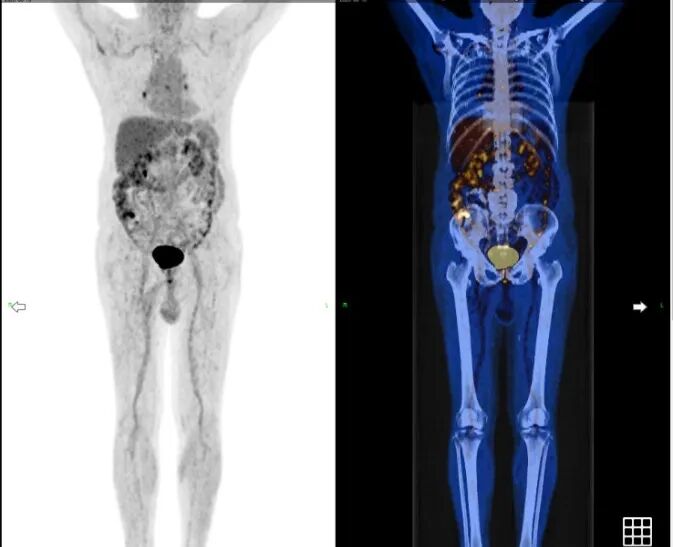

2025-05-22,2025-06-25日行第4、5周期治疗,患者2025-08接受PET-

图3 患者2025-08接受PET-CT检查结果